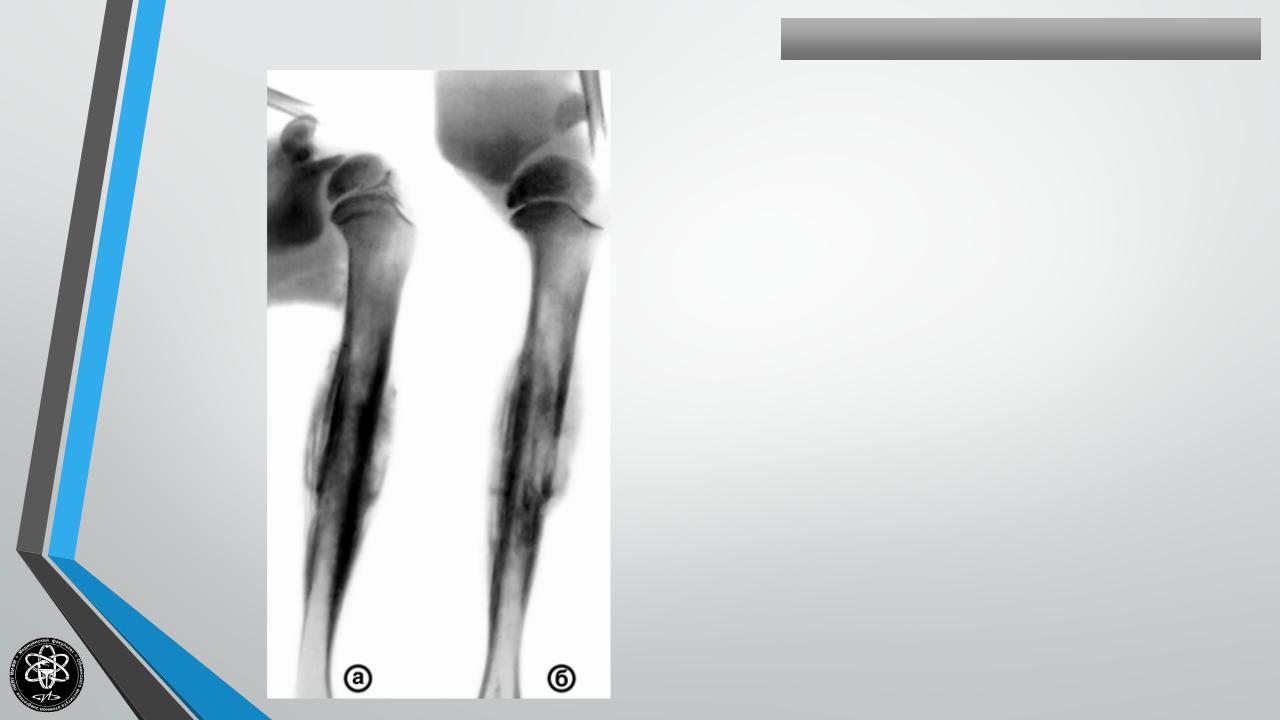

САРКОМАЮИНГА

Частные вопросы костной онкологии

Поражает молодых.

Излюбленная локализация — бедренная кость.

Клиника — боль, припухлость, температура, лейкоцитоз.

Расположение центральное.

Слоистость рентгеновской картины (“луковица”).

Метастазы в течение 2 месяцев в лимфоузлы, легкие.

Лечение — рентгентерапия.

Хирургическое лечение не предупреждает метастазирования.